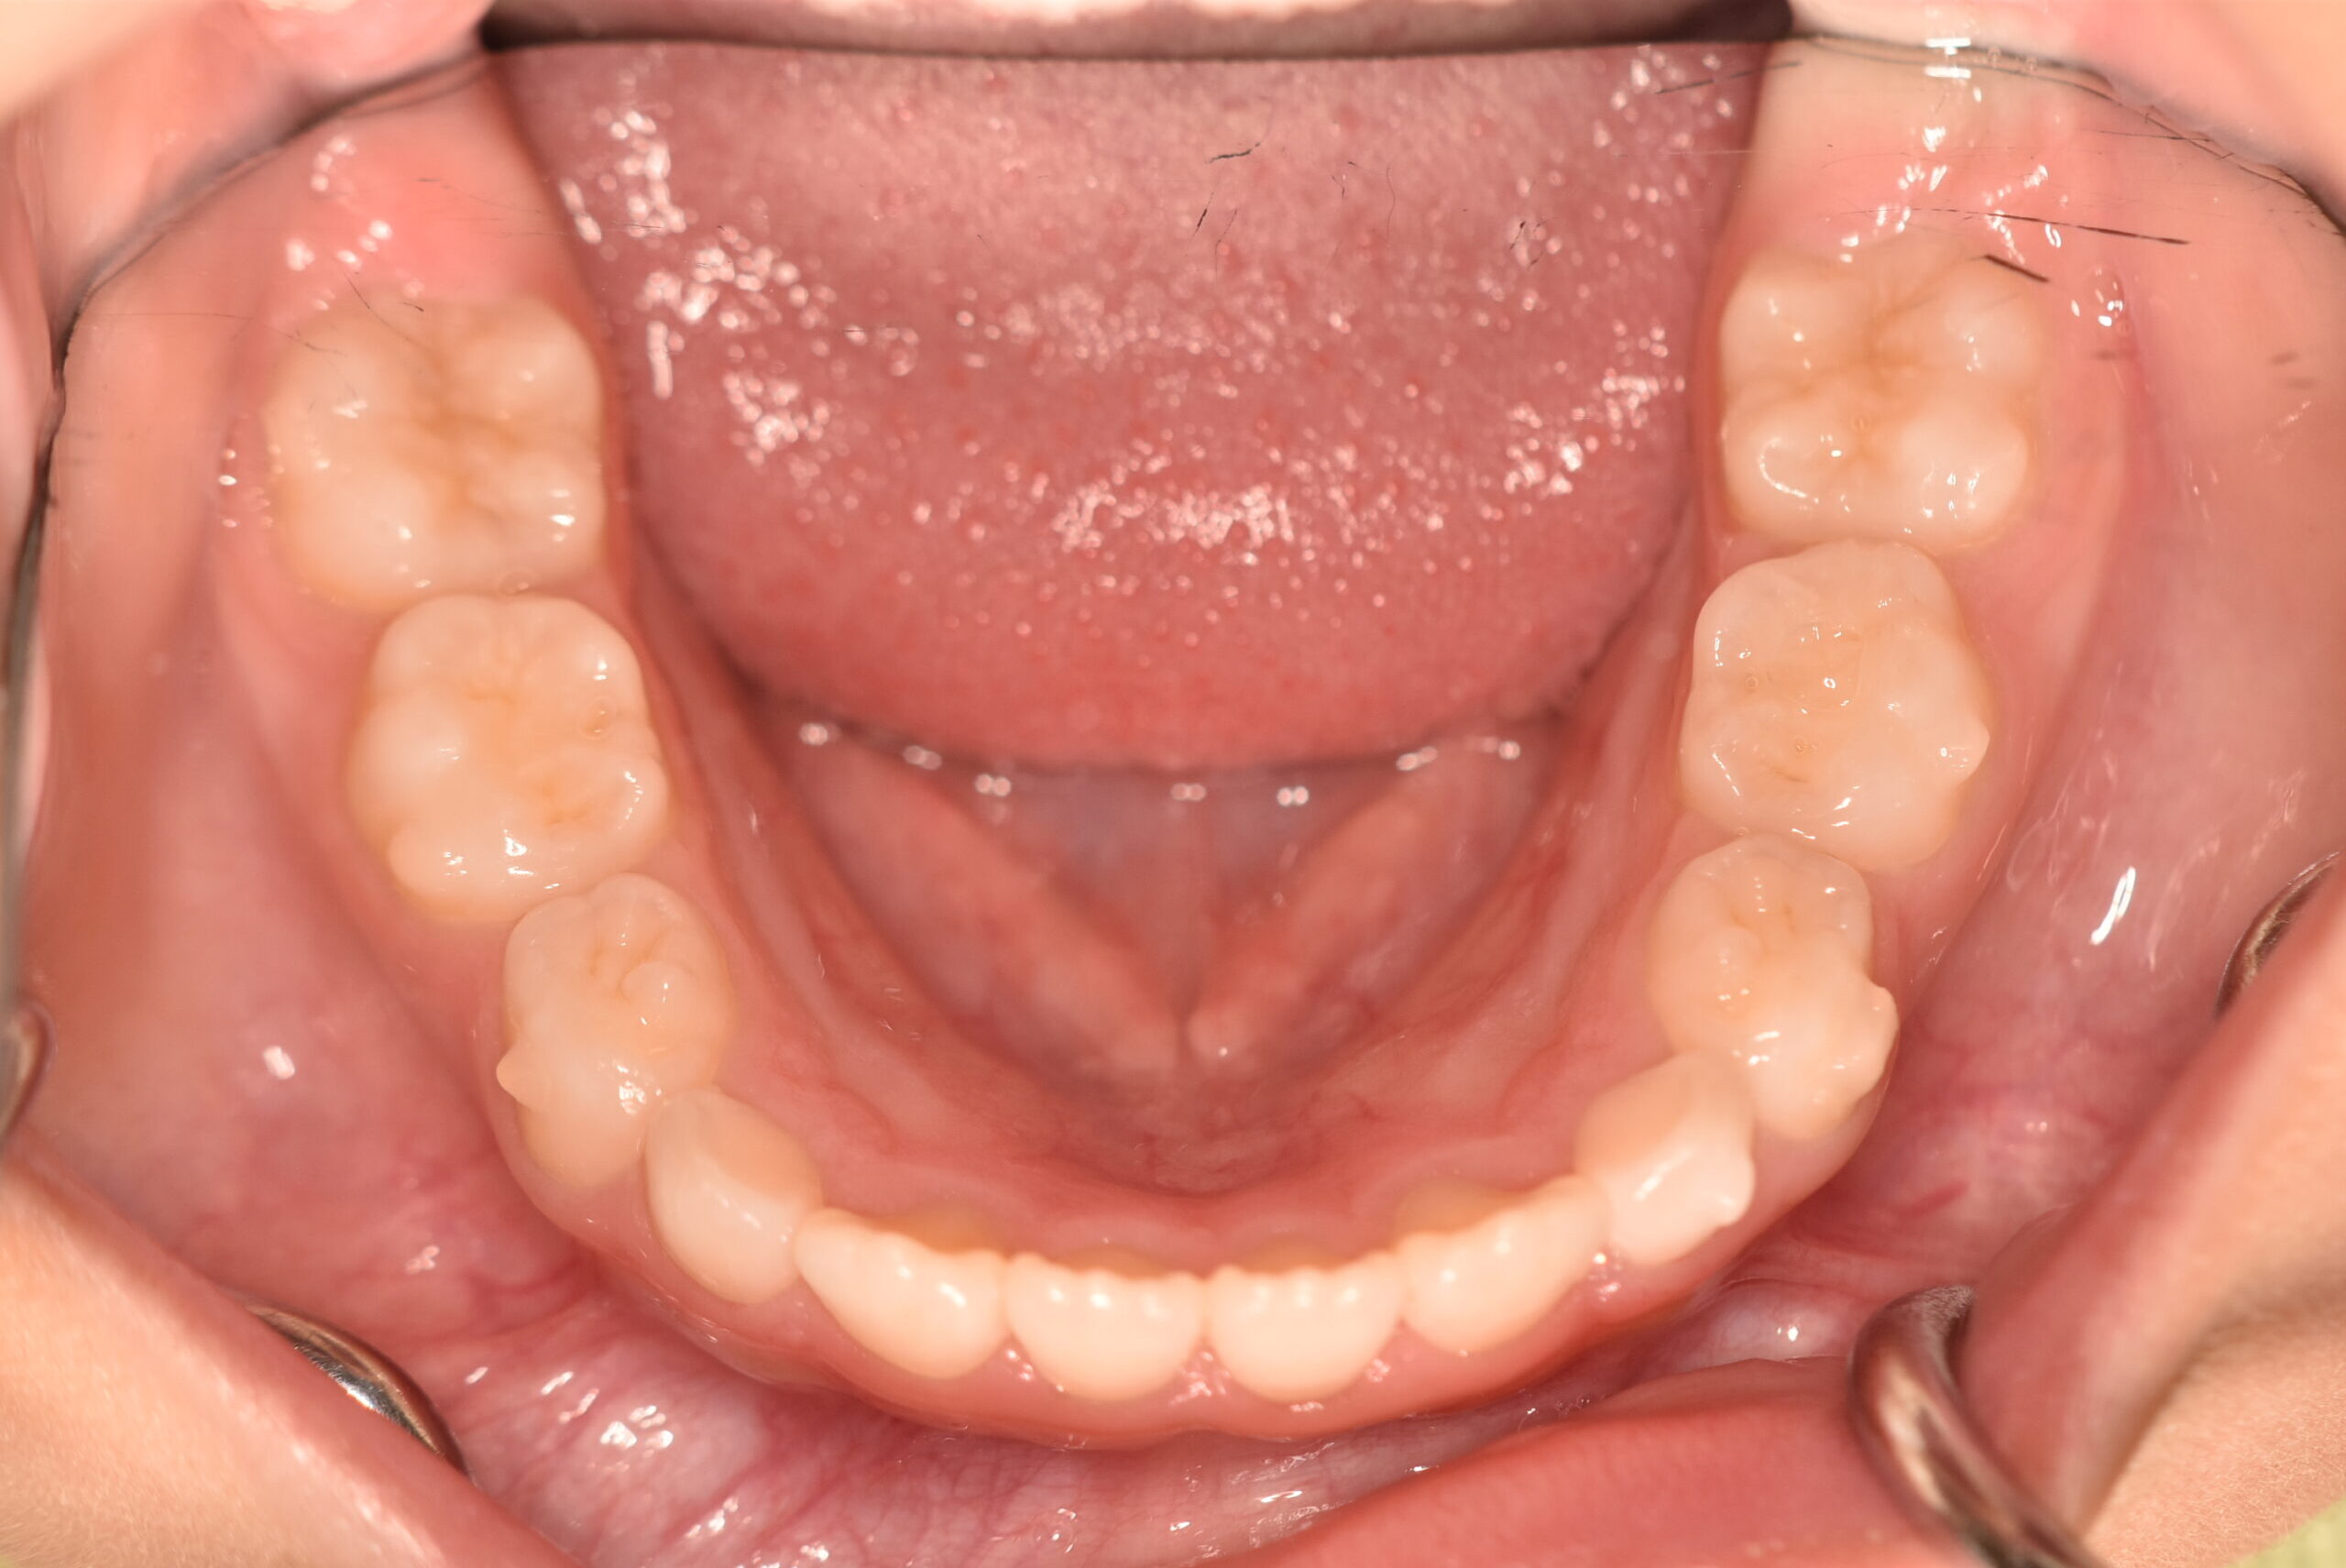

動的治療終了時

症例 症例 症例 症例

治療としてはマウスピース矯正(インビザラインファースト)で配列を行い、上下顎の側方拡大と萌出スペースを確保しました。

治療期間は、7ヶ月でした。

今後、側方歯生え変わりまで経過観察を行います。